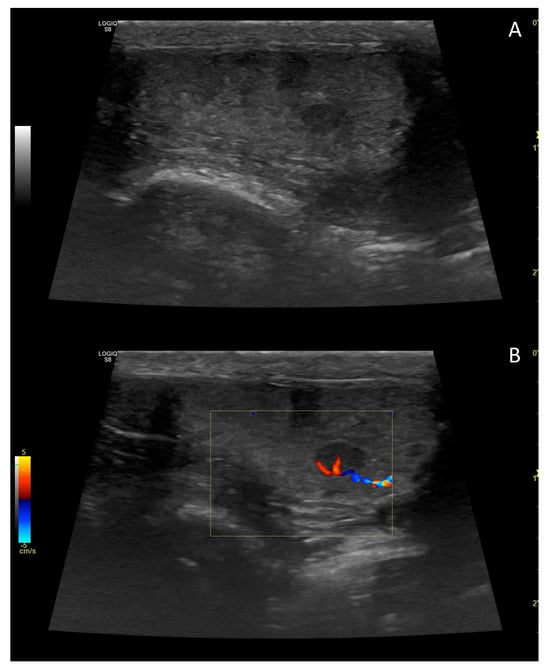

4. Colour Doppler and Power Doppler

4.1. Technology and Applications

4.2. Normal Findings

4.3. Relationship between Spectral Doppler Measurement and Dog’s Semen Quality

4.4. Abnormal Findings